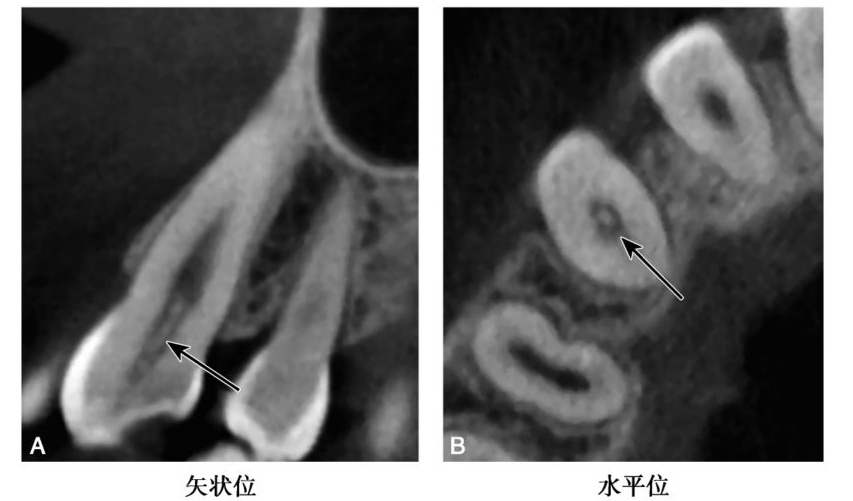

(2)前牙髓腔中的髓石一般呈条状或针状(图4)bccbch币。

图4 A3条索状钙化

CBCT示A3髓室至根管口处见针形高密度影(黑色箭头)